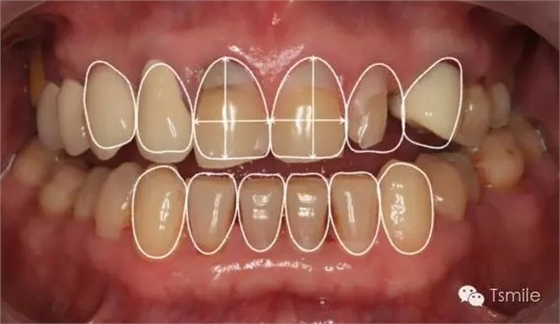

在前牙的美學(xué)分析中有四個(gè)最重要的美學(xué)影響因素,稱之為前牙美學(xué)四要素。包括上中切牙切緣的位置、上中切牙臨床冠的寬長(zhǎng)比、上中切牙齦緣的位置、上前牙的寬度比例。這四要素是影響前牙美學(xué)的主要因素,根據(jù)這四要素就可以簡(jiǎn)單、快速、準(zhǔn)確地分析患者前牙存在的美學(xué)缺陷。根據(jù)這四因素就可以準(zhǔn)確、直接地進(jìn)行患者前牙的美學(xué)修復(fù)設(shè)計(jì)。

例如面對(duì)一個(gè)牙列重度磨耗的美學(xué)修復(fù)患者,我們首先根據(jù)患者主訴和美學(xué)檢查形成美學(xué)設(shè)計(jì),然后通過(guò)數(shù)碼圖像表達(dá)美學(xué)設(shè)計(jì)思想,制作診斷蠟型,口內(nèi)制作診斷飾面,更加真實(shí)地表達(dá)美學(xué)設(shè)計(jì)。根據(jù)患者的要求和口內(nèi)試戴情況調(diào)改診斷飾面,最終確定美學(xué)修復(fù)設(shè)計(jì),即最終修復(fù)體的各種美學(xué)參數(shù)。接下來(lái)就是美學(xué)實(shí)現(xiàn)過(guò)程,在診斷飾面上進(jìn)行精確地牙體預(yù)備,制取印模和工作模型,技師按照最終診斷飾面的形態(tài)、大小和排列制作最終美學(xué)修復(fù)體,最后完成修復(fù)體粘接。